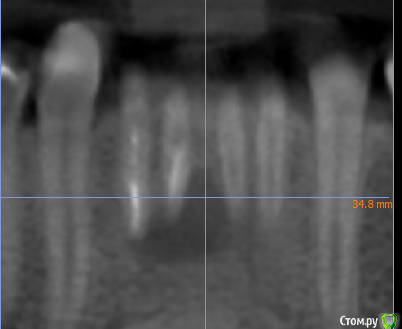

kramer Опубликовано 26 мая, 2020 Поделиться Опубликовано 26 мая, 2020 В общем, ситуация: 41, 42 бессимптомный периапикальный очаг, зуб 42 треснул. Биотип толстый. С точки зрения мезио-дистального расстояния влезает только 1 имплантат. Какой, на ваш взгляд, наиболее рациональный путь: а. Удаление обоих зубов, одномоментная имплантация 42, в последствии коронка с консолью б. Удаление обоих зубов, отсроченная имплантация в обл 42, в последствии коронка с консольюв. Удаление 41 с кюретажем, через пару месяцев удаление 42, одномоментная имплантация 42, в последствии коронка с консолью Ссылка на комментарий